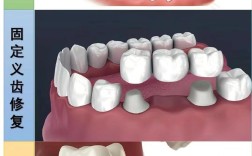

Q2:种植牙能用多久?会影响邻牙吗?

A:种植牙若维护得当,可使用10-20年甚至更久,与种植体品牌、骨质条件及口腔卫生习惯相关,相比传统烤瓷牙,种植牙无需磨损邻牙,独立植入牙槽骨,可恢复类似天然牙的咀嚼功能,对邻牙无负面影响,但需定期洁牙和检查,避免种植体周围炎。